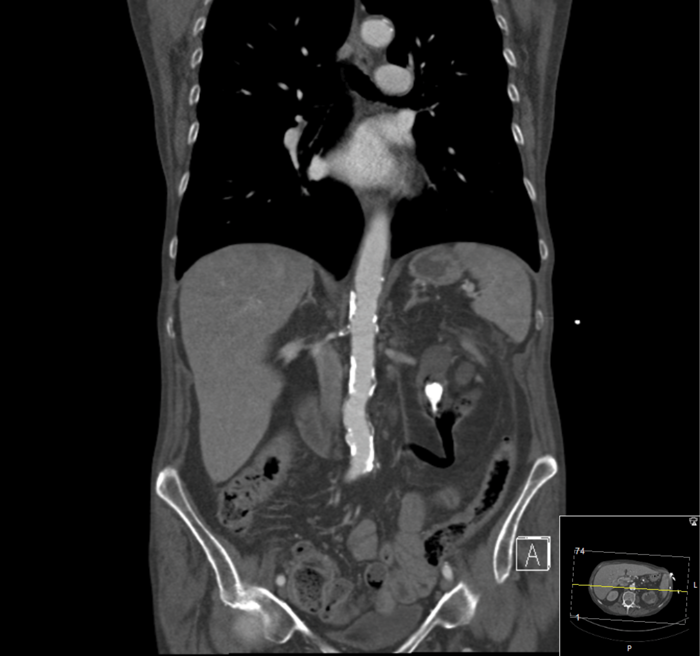

Case 4

A 57-year-old male presented with right flank pain. He had an established diagnosis of medullary sponge kidney and had been lost to follow-up. Serum creatinine was 114.

Figure 1: CT scout film demonstrating left ureteric stone on the opposite side to the patient’s pain.

Figure 2: 3D CT reconstruction demonstrating stone burden.